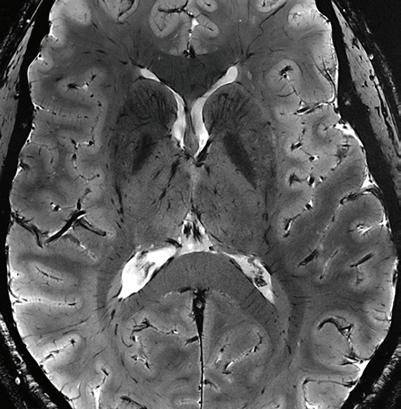

Connectome 2.0: Revealing Tissue Microstructure and Connectional Anatomy in the Brain with the Most Advanced Scanner for Diffusion MRI

A new state-of-the-art MRI scanner at the Martinos Center is set to provide unprecedented insights into the inner workings of the living human brain, with important implications for improving the diagnosis and treatment of neurological and mental disorders.

Dubbed “Connectome 2.0,” the scanner was developed through the support of the NIH BRAIN Initiative’s next-generation human imaging technology efforts to enable studies of neural tissue microstructure and circuits in the living human brain. It replaces the original Connectome scanner developed by Martinos researchers under the auspices of the NIH-funded Human Connectome Project.

“It’s an amazing device,” says Martinos Center director Bruce Rosen, MD, PhD. “It’s more than four times as powerful as the previous Connectome scanner, which was almost five times as powerful as anything else on the planet before we developed it.”

Imaging of the human “connectome,” as the complete set of connections within the brain has come to be known, dates to the mid-1990s, when Martinos researchers pioneered the MR imaging methods that made such imaging possible. “Diffusion” imaging enables imaging of axonal bundles— the wires that facilitate communication between different areas of the brain— by tracking water molecules as they travel along these white matter fibers.

Susie Huang, MD, PhD, a neuroradiologist at Mass General and the Martinos faculty member leading the Connectome 2.0 effort, is thrilled about the potential applications of the technology.

“Connectome 2.0 will dramatically enhance our ability to visualize the structure of the human brain by offering unprecedented spatial and diffusion resolution,” she says. “We are already seeing how the increased sensitivity of Connectome 2.0 to axonal and cellular

structure at the micron level is allowing us see surprising differences in how the human brain is organized at the individual level.”

Dr. Huang is now leading efforts to establish the Connectome 2.0 scanner as a unique shared resource facility and advance neuroscience collaborations around the world.